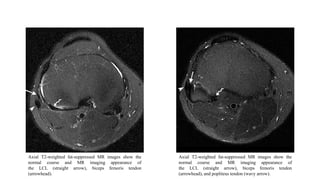

Axial T2-weighted fat-suppressed MR images show the normal

course and MR imaging appearance of the LCL (straight arrow),

biceps femoris tendon (arrowhead). The origin of the LCL is

immediately anterior to the femoral attachment of the lateral head

of the gastrocnemius tendon (curved arrow)

biceps femoris tendon (arrowhead), and popliteus tendon (wavy

arrow)

Axial T2-weighted fat-suppressed MR images show the

normal course and MR imaging appearance of

the LCL (straight arrow), biceps femoris tendon

(arrowhead).

(arrowhead), and popliteus tendon (wavy arrow).